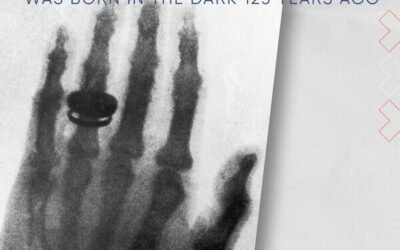

X-Rays: This invisible diagnostic light was born in the dark 125 years ago

Photographs. Sometimes they capture a moment. Sometimes they tell a story. And sometimes, a photograph can change the world. This month, join us as we revisit the discovery of the x-ray and how it would change patient care forever. How do x-rays work? And how did the...